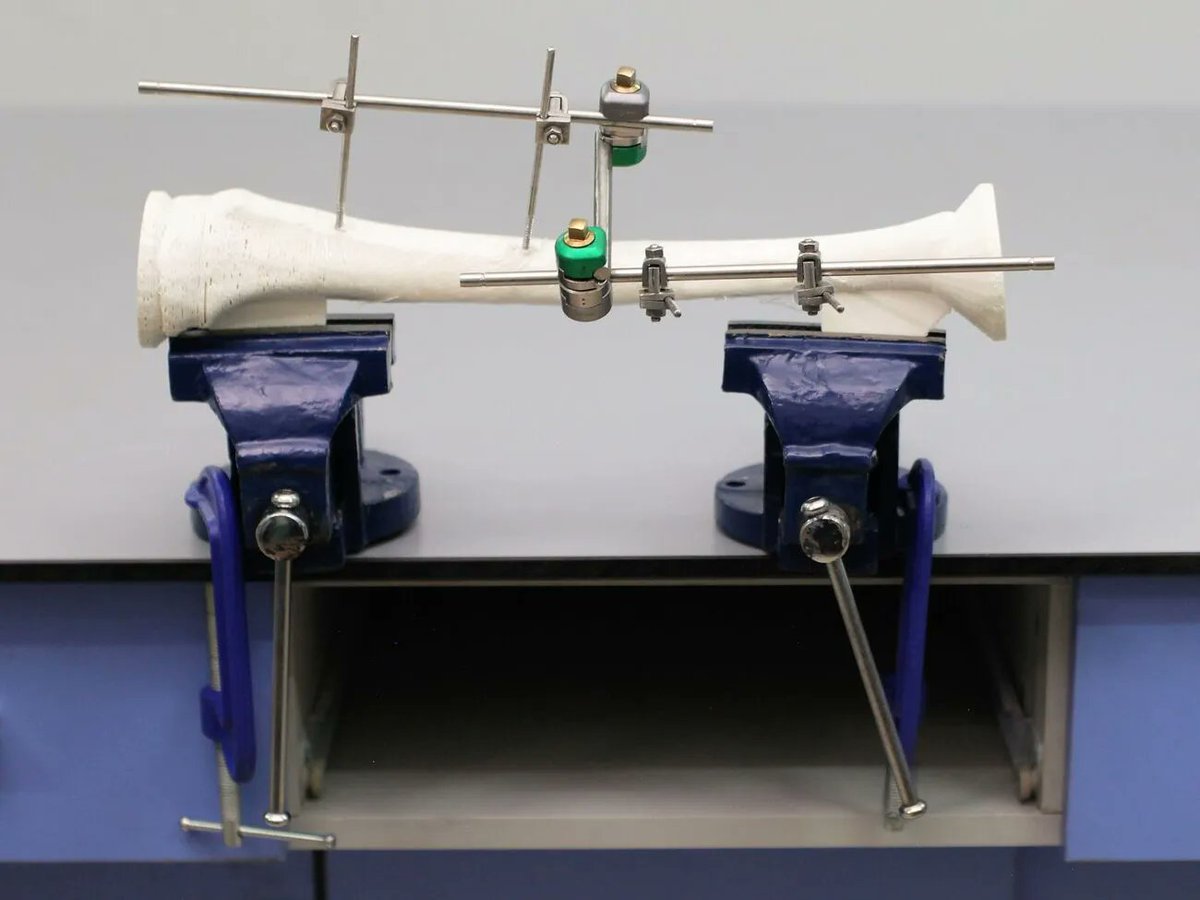

Join the #surgicaltrainingchallenge Prototype Showcase and meet the team designing a surgical training module to teach techniques to treat tibial fractures. buff.ly/3wZxIcC Julielynn Wong Medical Makers 3D4MD Habila Umaru

87% of serious injuries after earthquakes are orthopaedic. #SurgicalTrainingChallenge finalist Tibial Fracture Fixation seeks to expand orthopaedic skills in #LMICs so people get the care they need. buff.ly/3vwO12o Medical Makers Habila Umaru Julielynn Wong

#SurgicalTrainingChallenge finalist Habila Umaru visits ITESL FabLab to discuss 3D printing of bones for Tibial Fracture Fixation Medical Makers Julielynn Wong

#SurgicalTrainingChallenge finalist Habila Umaru & Intuitive Foundation’s catherinemohr examine a tibial fracture fixation training module. Learn more about their work: buff.ly/3ctkNv6

.Julielynn Wong and Habila Umaru set out to develop a module that teaches medical officers and non-orthopedic surgeons the essential surgical skills needed to treat tibial fractures. 💻 To learn more, visit appropedia.org/Tibial_Fractur… #GlobalSurgicalTrainingChallenge #RunnerUp